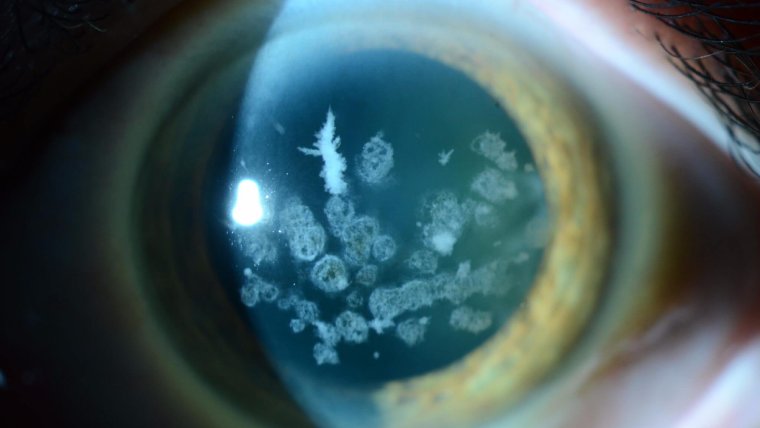

Characterized by the deposition of granular, amyloid, or mixed type opacities within the corneal stroma, GCD gradually impacts vision. The hallmark feature of this dystrophy is the presence of crumb-like granular deposits scattered throughout the cornea, primarily in the anterior stroma.

● Granules appear as white or grayish breadcrumb-like deposits.

GCD1, also known as classic granular corneal dystrophy or Groenouw type I, is characterized by the deposition of distinct granular opacities within the corneal stroma. These opacities are typically bread-crumb or snowflake-like in appearance and usually become visible within the first or second decade of life. The vision impairment in GCD1 is typically slow to progress, and severe vision loss is relatively rare.

3. Presence of corneal deposits: These appear as grayish or whitish granules within the cornea, often resembling bread crumbs or snowflakes. These granules may increase in number and size over time, contributing to the progressive nature of vision impairment.